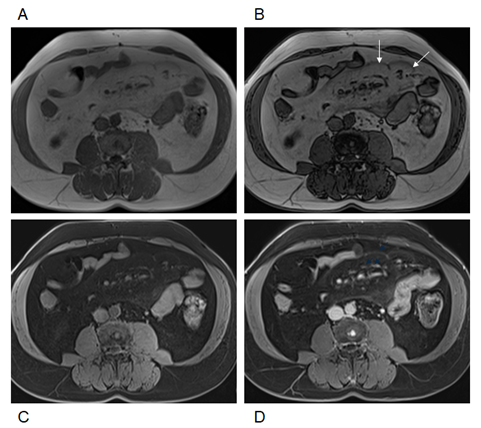

3. Moderate disease (Figure 1). Moderate duskiness of the mesentery with clear demarcation with a > 1 mm demarcated fibrous tissue boundary. Multiple lymph nodes internally with many > 1 cm.  There is no clear tethering of the bowel.

Figure 1 Moderate mesenteric panniculitis. Axial T2-weighted fat suppressed images (A). Axial T1-weighted in-phase (B) and out-of-phase (C), pre-contrast (D),arterial phase (E) and interstitial phase (F) GRE images. Moderate duskiness of the mesentery with clear demarcation with a demarcated fibrous tissue boundary (arrows, C). There is no clear tethering of the bowel.